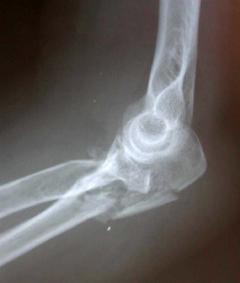

Περίπτωση 2ου ασθενούς

Προεγχειρητική

1 χρόνo μετά το χειρουργείο